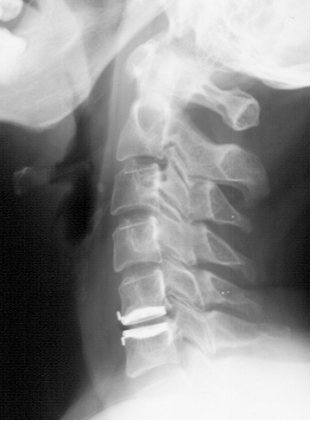

Korzyści płynące z dysksektomii wykonanej przy użyciu metody zilustrowanej poniższym pooperacyjnym bocznym radiogramem kręgosłupa szyjnego w stosunku do metod klasycznych sprowadzają się przede wszystkim do: